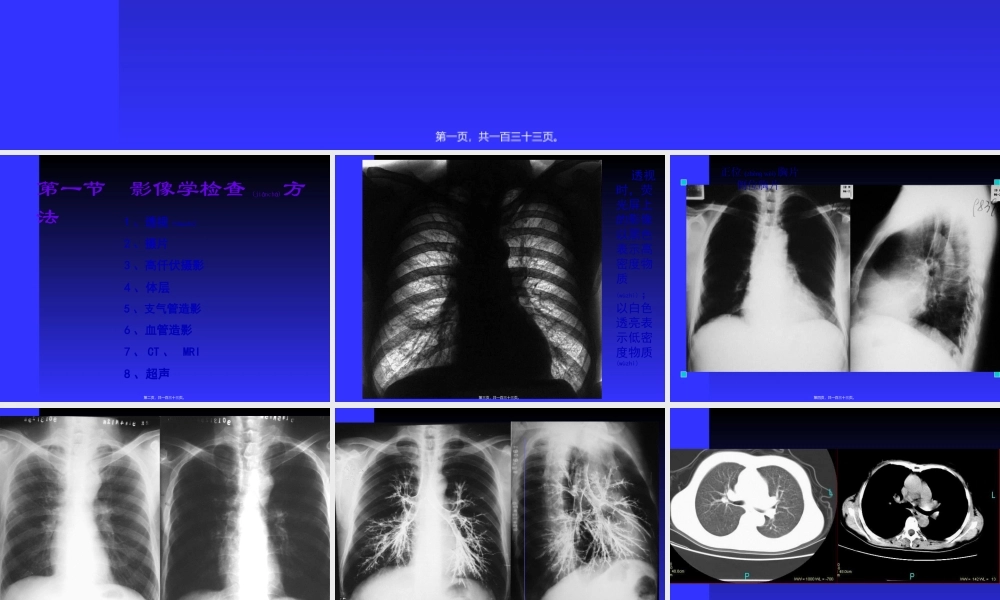

胸部(xiōnɡbù)影像诊断学呼吸系统(hūxīxìtǒnɡ)第一页,共一百三十三页。第一节影像学检查(jiǎnchá)方法1、透视(tòushì)2、摄片3、高仟伏摄影4、体层5、支气管造影6、血管造影7、CT、MRI8、超声第二页,共一百三十三页。透视时,荧光屏上的影像以黑色表示高密度物质(wùzhì);以白色透亮表示低密度物质(wùzhì)第三页,共一百三十三页。正位(zhènɡwèi)胸片侧位胸片第四页,共一百三十三页。高千伏摄影(shèyǐng)使气管内病变显示(气管癌)第五页,共一百三十三页。支气管造影(zàoyǐng)第六页,共一百三十三页。GUIYANGMEDICALCOLLEGEGUIYANGMEDICALCOLLEGECT用于胸部检查,可根据(gēnjù)需要,调节窗宽窗位,显示不同内容第七页,共一百三十三页。第二章正常(zhèngcháng)胸部影像学表现第八页,共一百三十三页。思考(sīkǎo)重点:能在X线胸片上留下影像的胸壁软组织有哪些?第九页,共一百三十三页。壹胸廓一.胸壁软组织胸锁乳突肌锁骨上皮肤(pífū)皱折胸大肌乳房和乳头第十页,共一百三十三页。胸锁乳突(rǔtū)肌和锁骨上皮肤皱折第十一页,共一百三十三页。胸大肌第十二页,共一百三十三页。肩胛骨和乳头(rǔtóu)第十三页,共一百三十三页。乳房(rǔfáng)第十四页,共一百三十三页。乳房(rǔfáng)似肺炎第十五页,共一百三十三页。乳房(rǔfáng)似胸腔积液第十六页,共一百三十三页。二.骨性胸廓锁骨胸骨(xiōnggǔ)肋骨肩胛骨胸椎第十七页,共一百三十三页。胸骨(xiōnggǔ)柄勿误为纵隔增宽第十八页,共一百三十三页。叉状肋第十九页,共一百三十三页。肋骨(lèigǔ)联合畸形第二十页,共一百三十三页。二胸膜水平(shuǐpíng)叶间裂隙斜裂叶间胸膜(细线状致密影)第二十一页,共一百三十三页。水平(shuǐpíng)叶间胸膜第二十二页,共一百三十三页。第二十三页,共一百三十三页。第二十四页,共一百三十三页。第二十五页,共一百三十三页。三膈肌位置(wèizhi)运动升高或降低原因波浪膈心膈角肋膈角第二十六页,共一百三十三页。心膈角后肋膈角波浪(bōlàng)膈侧肋膈角前肋膈角后肋膈角第二十七页,共一百三十三页。正常(zhèngcháng)膈肌和各肋膈角、心膈角第二十八页,共一百三十三页。波浪(bōlàng)膈第二十九页,共一百三十三页。四肺肺叶(肺段、肺小叶、肺腺泡)气管(qìguǎn)与支气管(qìguǎn)肺实质肺间质肺野第三十页,共一百三十三页。思考重点:解释下列名词:肺实质(shízhì)肺间质肺野...